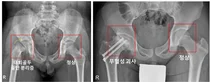

[사진] 우측 고관절에 대퇴골두 골단 분리증 및 무혈성 괴사가 발생한 소아청소년 환자의 X-ray 최근 국내 연구진이 소아청소년 내분비질환 환자에서의 대퇴골두 골단 분리증의 발병률을 세계 최초로 규명했다.